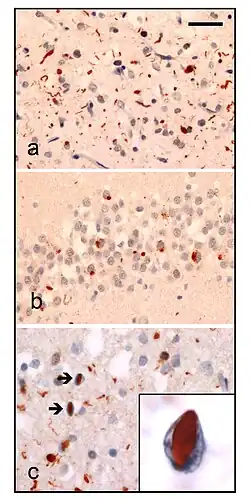

Neuropathologic analysis of brain tissue from FTLD-TDP patients. Ubiquitin immunohistochemistry in cases of familial FTLD-TDP demonstrates staining of (a) neurites and neuronal cytoplasmic inclusions in the superficial cerebral neocortex, (b) neuronal cytoplasmic inclusions in hippocampal dentate granule cells, and (c) neuronal intranuclear inclusions in the cerebral neocortex (arrows). Scale bar; (a) and (b) 40 μm, (c) 25 μm, insert 6 μm.